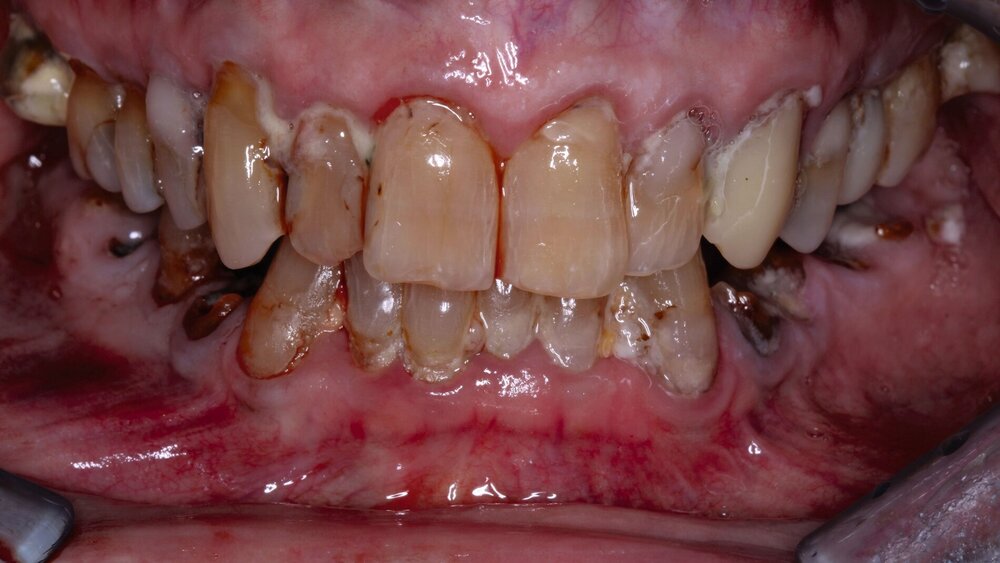

„Pflegebedürftige und Menschen mit Behinderungen können oft nicht mehr eigenverantwortlich für ihre Mundhygiene sorgen, die im Schnitt schlechter als die der übrigen Bevölkerung ist", betont Martin Hendges, Vorsitzender des Vorstandes der KZBV.

"Das Risiko für Karies-, Parodontal- und Mundschleimhauterkrankungen ist bei diesen Patienten besonders hoch. Daher ist es umso wichtiger, sie regelmäßig und zielgruppenspezifisch zahnmedizinisch zu versorgen. Speziell für ihre Bedarfe haben wir zugeschnittene Versorgungskonzepte entwickelt; das Leistungsspektrum wurde in den vergangenen Jahren erheblich erweitert. Die jetzt vorliegenden Daten zeigen den Erfolg und die Notwendigkeit dieses wichtigen Versorgungsangebots.“

Im Fokus der koordinierten zahnärztlichen Versorgung stehe die Verbesserung von Prävention und Therapie und damit eine gesteigerte Lebensqualität von Pflegebedürftigen und Menschen mit Behinderungen. Eine verbesserte Mundgesundheit sei dabei nicht nur von zentraler Bedeutung für die Allgemeingesundheit, Essen und Sprechen würden ebenfalls erleichtert. Das wirke sich nicht zuletzt positiv auf soziale Teilhabe aus, so Hendges.